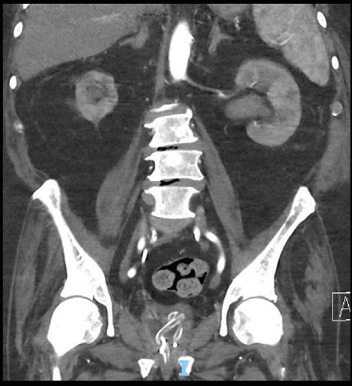

目的:膀胱内自发打结是一种罕见的导尿管并发症。我们提出了一种新的内窥镜治疗方法来处理输尿管支架周围自发打结的导尿管。主题:一名79岁男性因意识不清和急性肾衰竭来到急诊科。他的背景是转移性去势抵抗性前列腺癌。他的相关梗阻性尿路病变通过长期右侧7-Fr r输尿管支架治疗,最后一次更换是在1个月前,并长期18-Fr留置导尿管。CT静脉肾盂造影清楚地显示他的留置导管缠结并穿过右输尿管支架的远端膀胱部分。结果:经皮肾造口术对左肾进行减压后,在透视下尝试用各种导线和导尿管拔出尿管。患者随后接受全身麻醉,并用Mauermayer石粉碎机通过25-Fr通路鞘成功地将结部分去除。结论:内窥镜技术,如使用石粉碎机可能有利于去除困难和复杂的导管结,正如本病例所示。导管打结应始终考虑,如果功能或试图去除导管是异常的,并及时转诊到泌尿科医生。

Objective: Spontaneous intravesical knotting is a highly infrequent complication of urinary catheters. We present a novel endoscopic treatment approach to managing a spontaneously knotted urinary catheter around a ureteric stent. Subject: A 79-year-old man presented to the Emergency department with confusion and acute renal failure. His background was significant for metastatic castrate-resistant prostate cancer. His associated obstructive uropathy was managed with a long-term right 7-Fr Rüsch ureteric stent, last changed 1 month prior and a long-term 18-Fr indwelling catheter. A CT intravenous pyelogram clearly demonstrated his indwelling catheter knotted around and through the distal intravesical portion of an appropriately positioned right ureteric stent. Results: Following decompression of the left kidney via percutaneous nephrostomy, attempts were made to remove the urinary catheter under fluoroscopy with a variety of wires and introducers. The patient then underwent a general anesthesia, and the knot was successfully removed piecemeal with a Mauermayer stone crusher via 25-Fr access sheath. Conclusion: Endoscopic techniques such as the use of a stone crusher may be beneficial for the removal of difficult and complex catheter knots as demonstrated in this case. Catheter knotting should always be considered if the functioning or attempted removal of the catheter is abnormal and timely referral to a urologist is made.